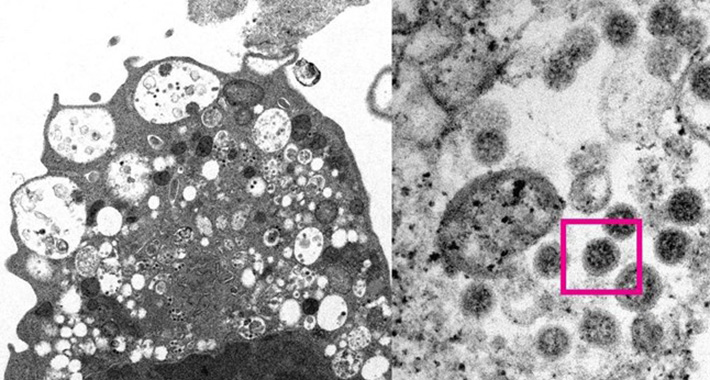

To je dijelom rezultat imunološke zaštite cijepljenjem među osobama starijim od 5 godina, boostera, kao i potencijalno niže virulencije samog virusa, navodi se u izvještaju. Druge studije sugerirale su da je varijanta manje sposobna prodrijeti duboko u pluća.